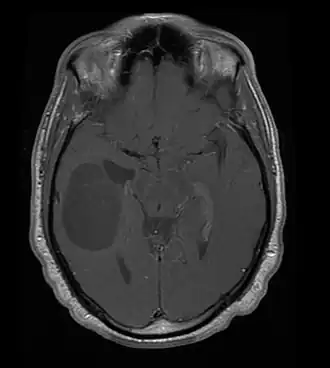

![]() Oligodendroglioma (zona hipodensa u oscurecida de la izquierda), resonancia magnética. | ||